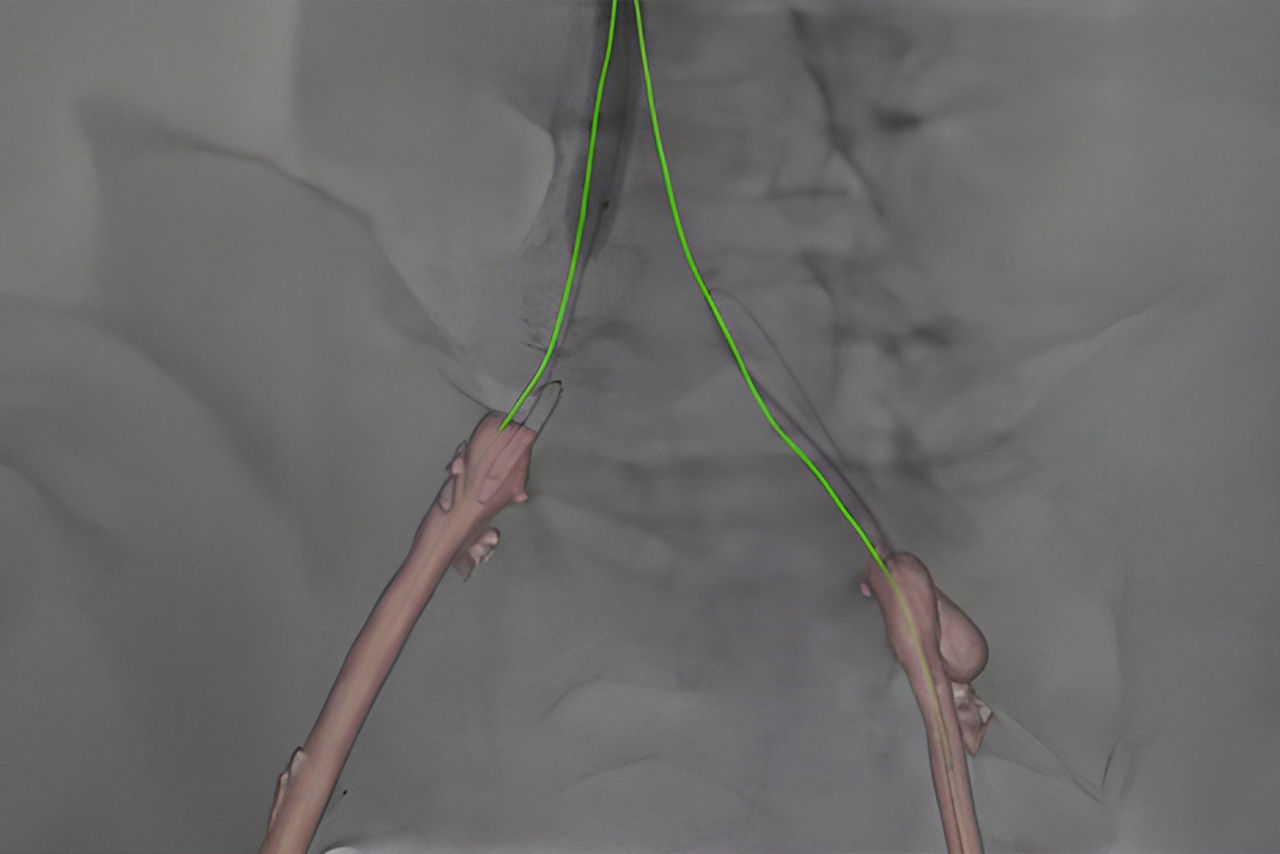

Guide

Select from the sub-volumes of vessels, centerlines, calcifications and landmarks to overlay on live fluoroscopy for 3D fusion guidance, with digital zoom, to guide recanalization.

Access

Use DSA images on larger Field Of View to image the entire anatomy of interest.